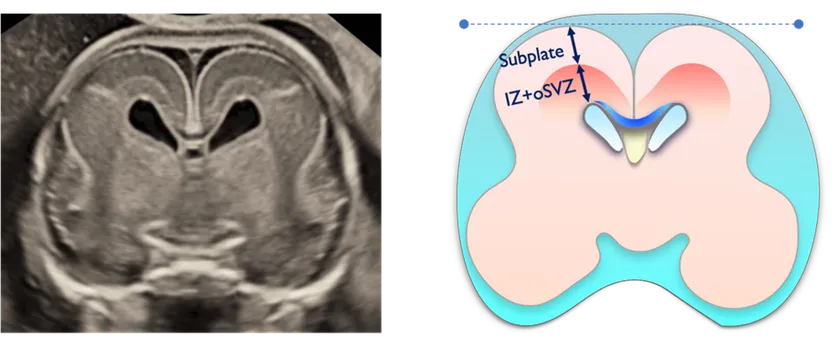

夫 律子院長が発表した研究は、胎児の脳における「サブプレート」と呼ばれる脳層に着目したものです。サブプレートは胎児期の一定の時期にしか観察されることがない特殊な脳層で、ヒトの大脳皮質形成初期においてニューロンの移動や神経回路の形成に重要な役割を果たし、神経発達の鍵を握る構造として注目されています。このサブプレートに着目して実際の胎児での観察実績をもつのは現在のところ世界でもクリフム出生前診断クリニックだけです。※当院調べ

■研究概要

対象:1,000人以上の胎児

方法:高精度3D経膣脳神経超音波による脳の詳細計測

結果:先天異常を持つ胎児群を複数のグループに分類し、サブプレートの発達パターンを比較分析した結果、グループ間で明確な発達の違いを確認。

本研究の進展により、胎児期における個別の神経発達予測が可能となり、従来の画一的な診断から脱却した胎児期からの個別化医療の実現が期待されます。

胎児脳サブプレート研究